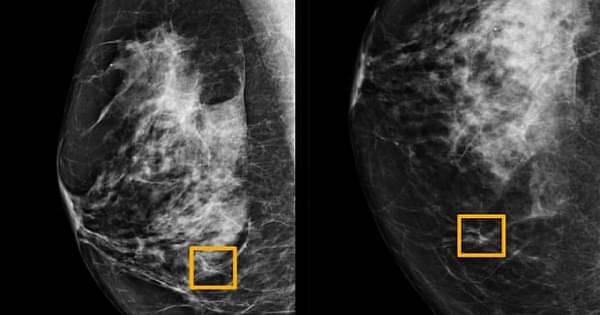

Комбинирование неврологических препаратов и препаратов для снижения давления уменьшает риск развития опухолей молочных желез у мышей Добавление лекарства для лечения эпилепсии, биполярного расстройства и мигреней в препарат для снижения кровяного давления изменило некоторые паттерны развития рака молочных желез у мышей, имевших высокий...